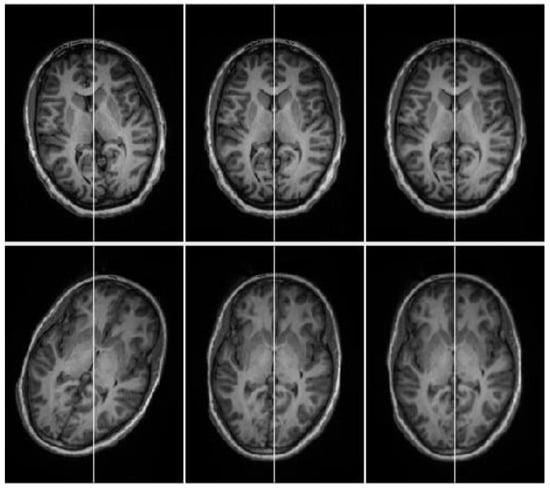

In short, all the promising results given by the proposed algorithm indicates that the developed technique has the highest accuracy and consistency in extracting the MSP. Finally, the results of automatic MSP detection and tilt correction (recenter and reorientation) in brain MRIs are displayed in Figure 15, where the first row represents the tilted slices of the three distinct brain volumes. After computing the parameters of the MSP and affine transformation, we reoriented and recentered the brain volumes. The corrected volume images are displayed in the second row of Figure 15.

Figure 15.

The results of symmetric detection and tilt correction (realignment of the brain head volume). The input head volumes images are in the first row and reoriented (recentered) head volumes images are in the second row.